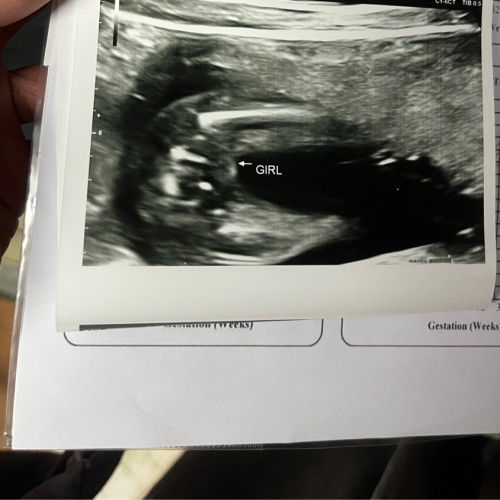

Sekarang dah nak masuk 38 minggu and memang berharap baby keluar awal dari tarikh due. Tapi tiba-tiba terkena buasir yg teruk sangat susah nak duduk, jalan or bangun dari baring. Senang cerita pergerakan memang terbatas 😭 first time saya kena seteruk ini. mcm2 ubat saya dah try still takde perubahan. Rendam air garam pun dah. Ada tak tips lain utk kecutkan buasir ni? ☹️#please_help